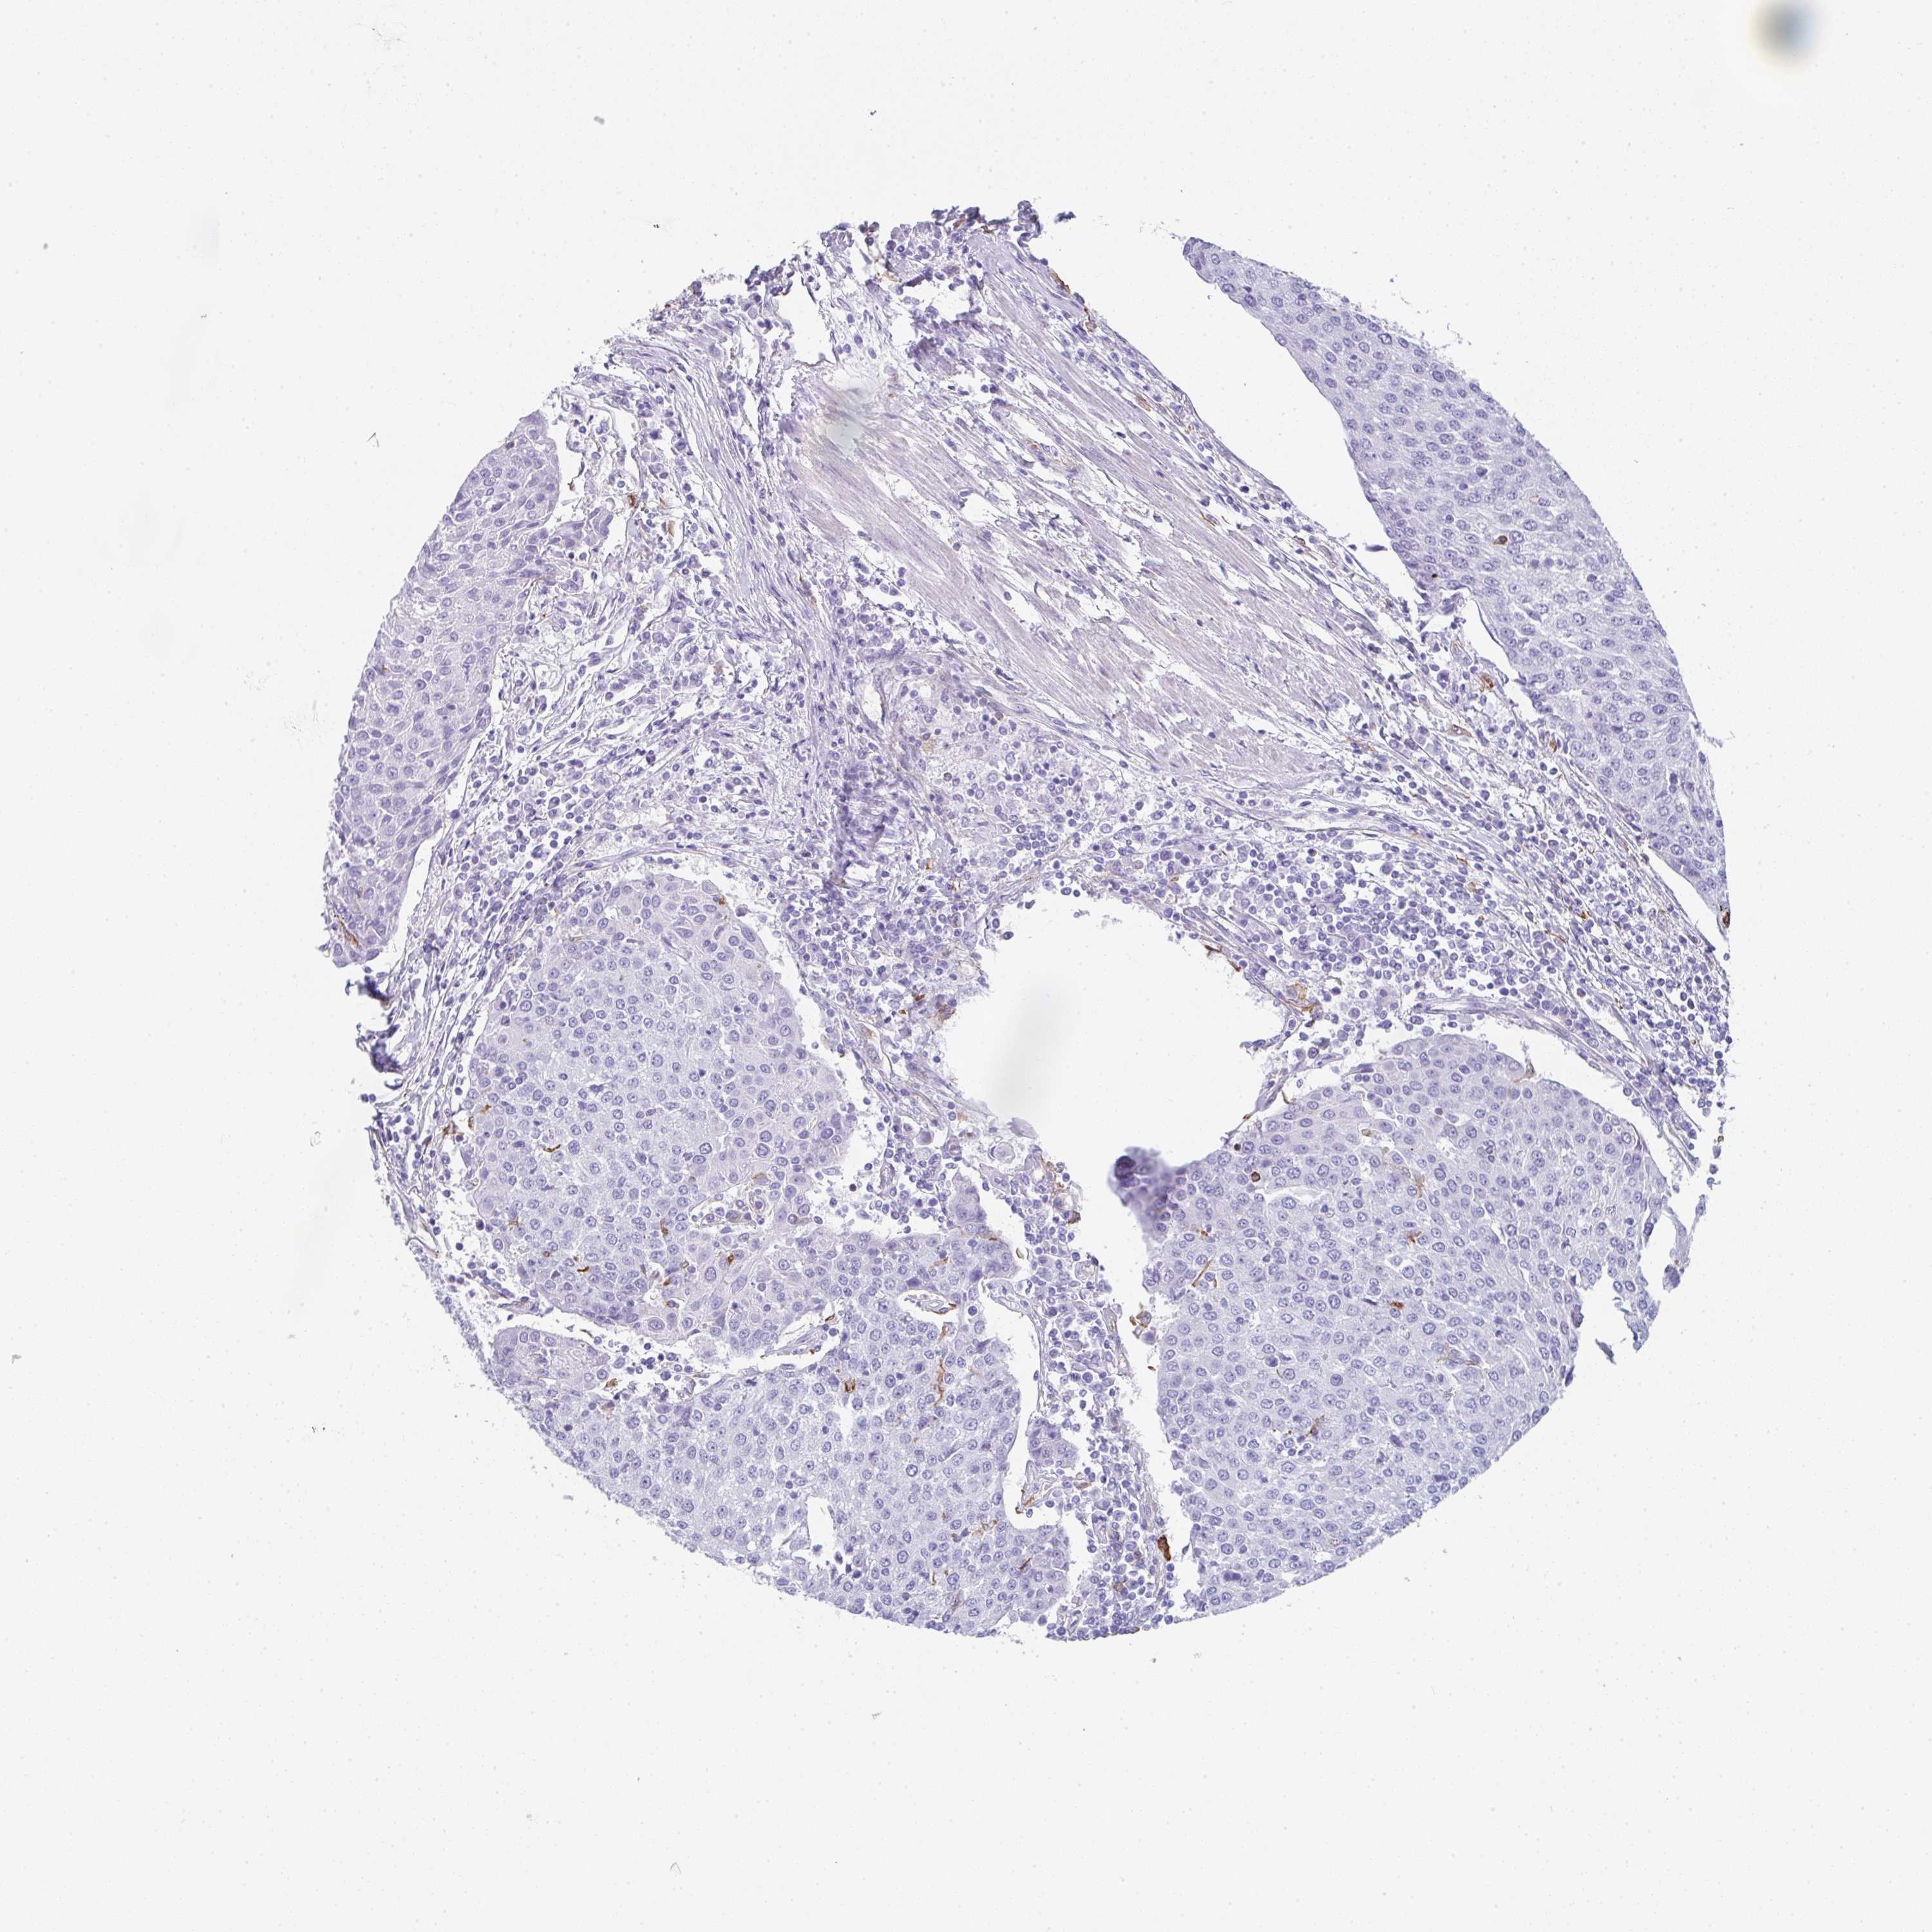

UROTHELIAL CANCER - Protein expressioni

A mouse-over function shows sample information and annotation data. Click on an image to view it in a full screen mode. Samples can be filtered based on level of antibody staining by selecting one or several of the following categories: high, medium, low and not detected. The assay and annotation is described here.

Antibody stainingi

Antibody staining in the annotated cell types in the current human tissue is reported as not detected, low, medium, or high, based on conventional immunohistochemistry profiling in selected tissues. This score is based on the combination of the staining intensity and fraction of stained cells.

Each image is clickable and will lead to virtual microscopy that enables deeper exploration of all samples and also displays staining intensity scores, fraction scores and subcellular localization as well as patient and tissue information for each sample.

Antibody HPA051452

Antibody HPA056940

Staining

High

Medium

Low

Not detected

Intensity

Strong

Moderate

Weak

Negative

Quantity

>75%

75%-25%

<25%

None

Location

Nuclear

Cytoplasmic/membranous

Cytoplasmic/membranous,nuclear

Urothelial carcinoma, High grade

Urothelial carcinoma, Low grade